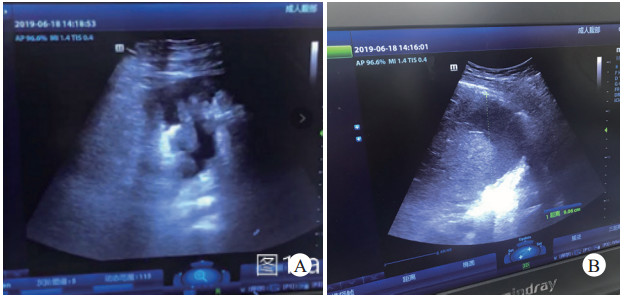

1.3 辅助检查2019年6月18日00时30分CT提示右侧第6、7肋骨前段骨折,胸6椎体压缩性骨折,右侧少量气胸,肝上间隙见少量液体密度影,腰2、3、5椎体右侧横突骨折,骶骨右侧耳状面、右侧髂骨、双侧耻骨上下支骨折。2019年6月18日14时00分床旁彩超提示胸腹腔大量积液,考虑肝损伤。

此时,患者入院14 h输血输液15 000+ mL(ARh+红细胞悬液34 U, 血浆2 400 mL, 血小板2治疗量, 冷沉淀20治疗量),患者HR 150次/min,BP90/50 mmhg, 呼吸机辅助呼吸,去甲肾上腺素1.2 μg/(kg·h), 尿量20 mL/h.血气分析(6月18日12时43分):pH 6.9、乳酸10.4 mmol/L、K+ 5.4 mmol/L,血红蛋白59 g/L。患者少尿,休克进行性加重、出血未控制。5G网络实时传输超声图像发现:双侧胸腔积液(图 2B),腹腔大量积液(图 2A),腹腔内出血,骨盆骨折,专家组高度怀疑腹腔内活动性出血。

| 图 2 A:腹腔积液;B:胸腔积液 |